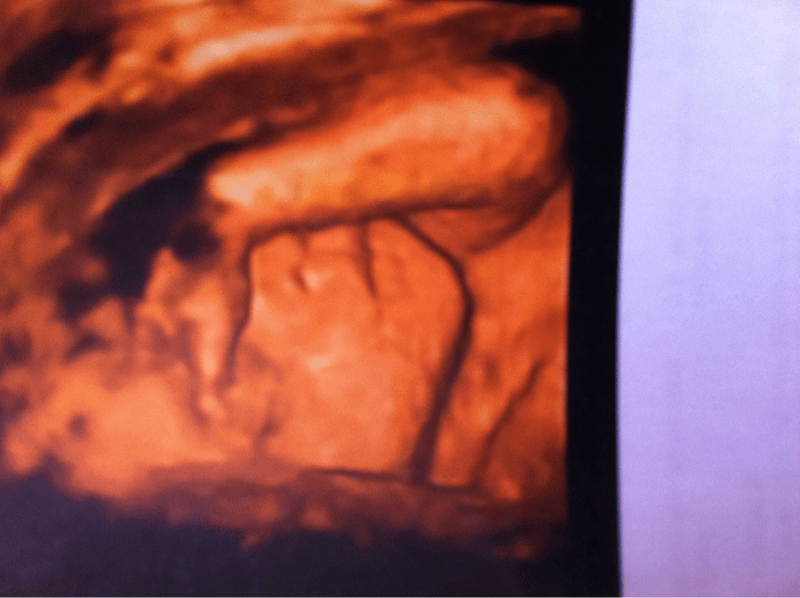

Voilà ct pour ma fille

• image-3637013094.png

image-3637013094.png

176.1 KB · Affichages: 33